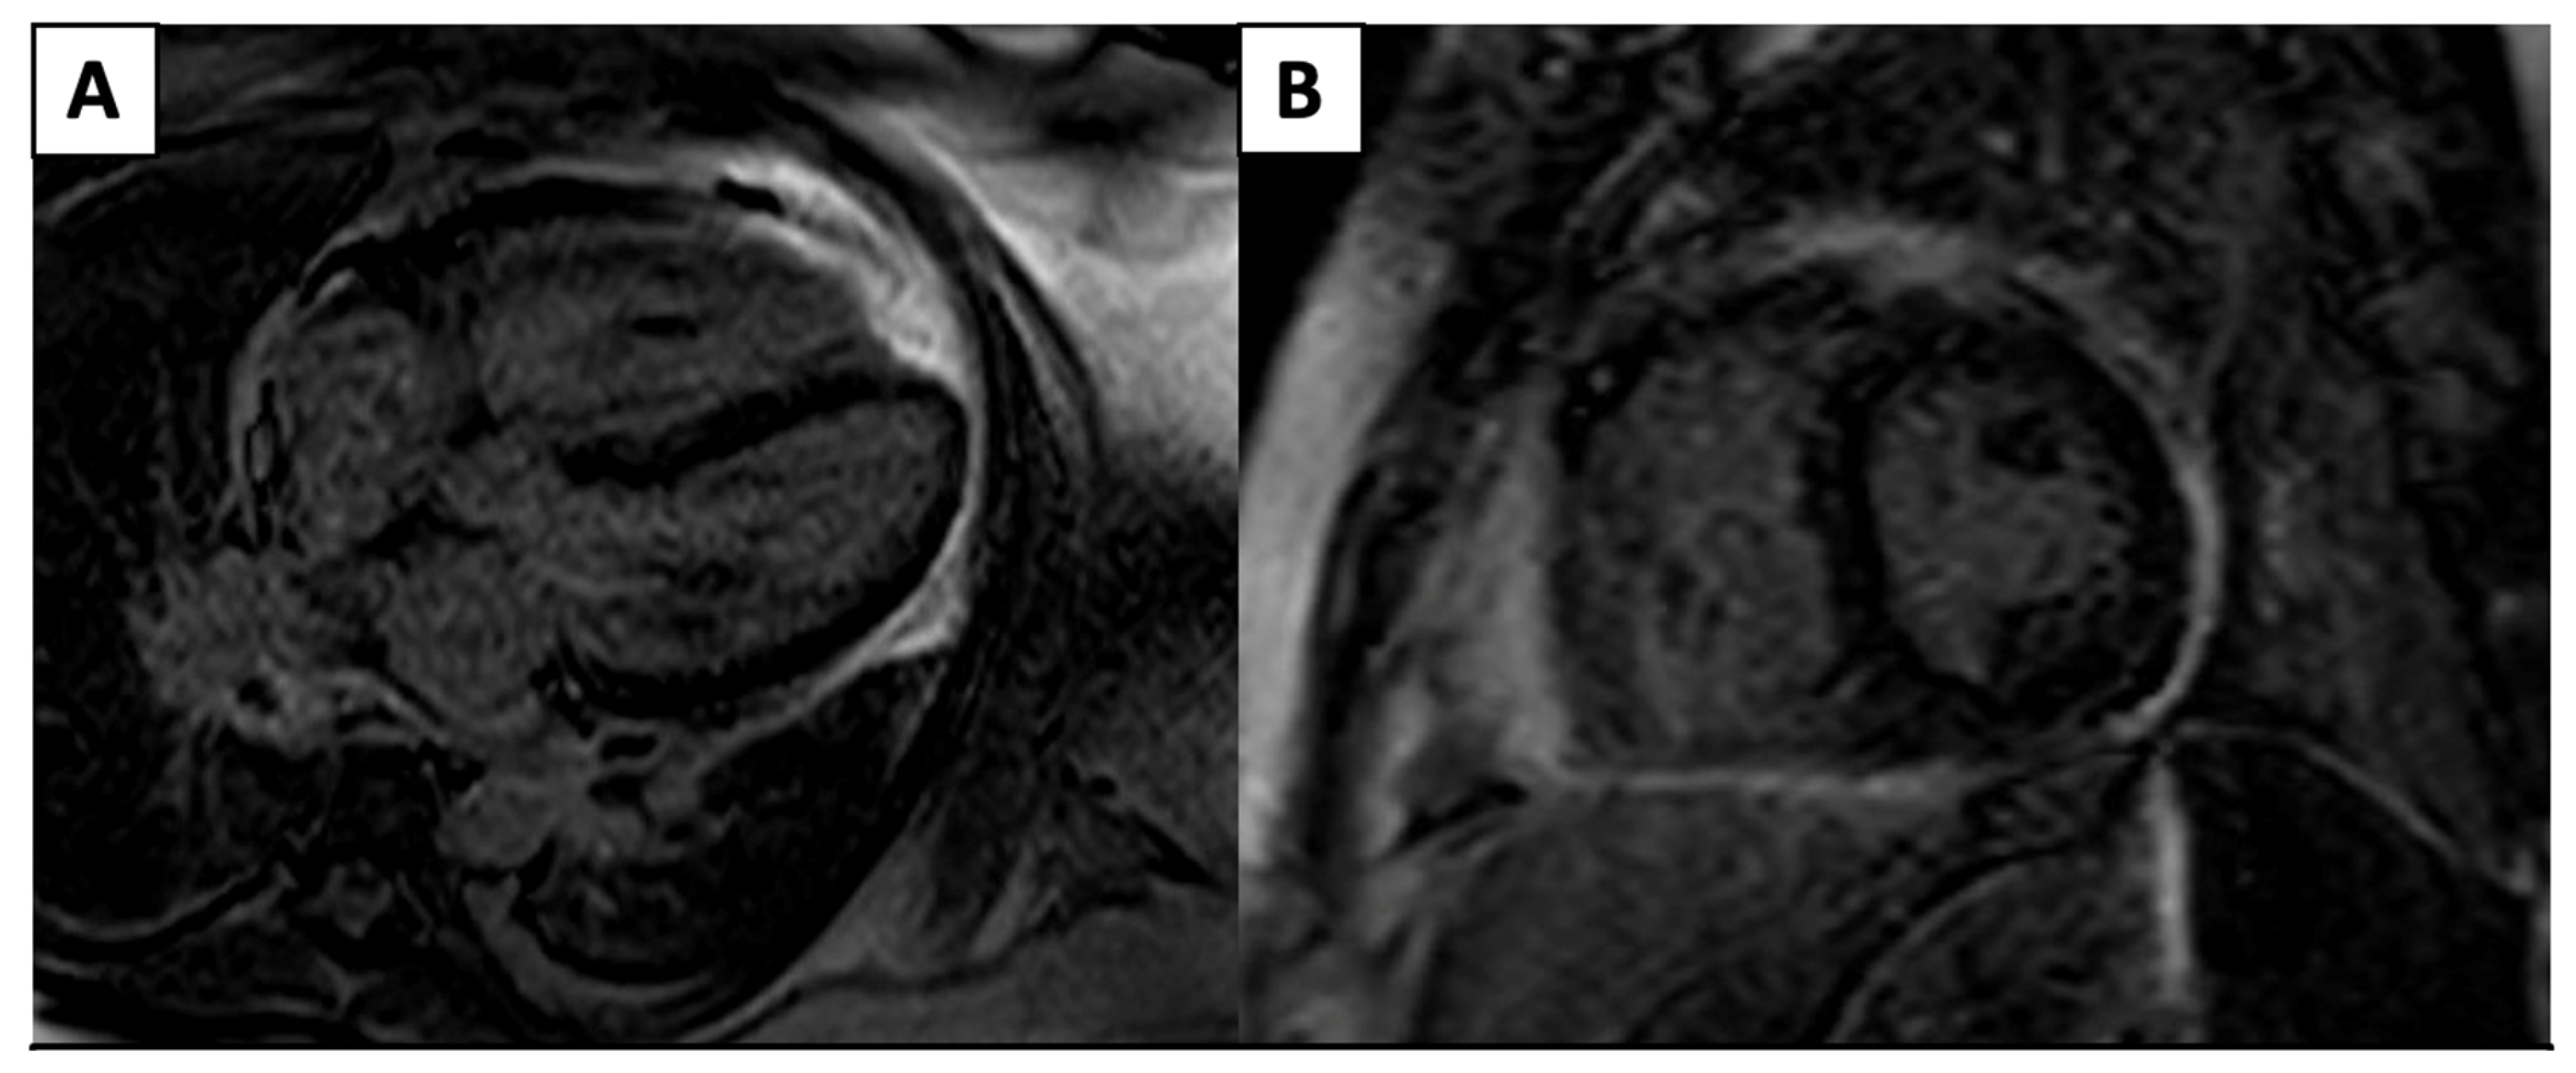

| Cardiac CT | ![]() | Left-anterior descending artery on cardiac CT |